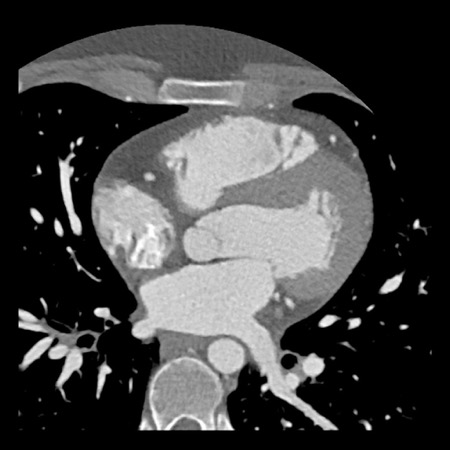

case 2 – CAD-RADS 5/P2/S

First, scroll through the CTA images.

How would you describe the findings on the coronary CTA?

The findings are:

- Stent in the mid

LAD with low-attenuation within the stent suggestive of minimal in-stent

restenosis (<25%). Non-calcified plaque distal to the stent

causing mild stenosis (25-49%). Notice bridging on a short segment in

the distal LAD. - Non-calcified

plaque in the LCX causing mild stenosis (25-49%). - Occlusion of the

proximal OM1 branch with distal filling. - Calcified and

non-calcified plaques in the proximal RCA causing mild (25-49%) stenosis. - Total plaque burden

is moderate based on SIS (four segments including proximal RCA, mid LAD, prox

LCX and OM1).

Due to the occlusion of OM1 branch and presence of the stent, this case

reads as CAD-RADS 5/P2/S, which means that this patient needs further

diagnostic workup.